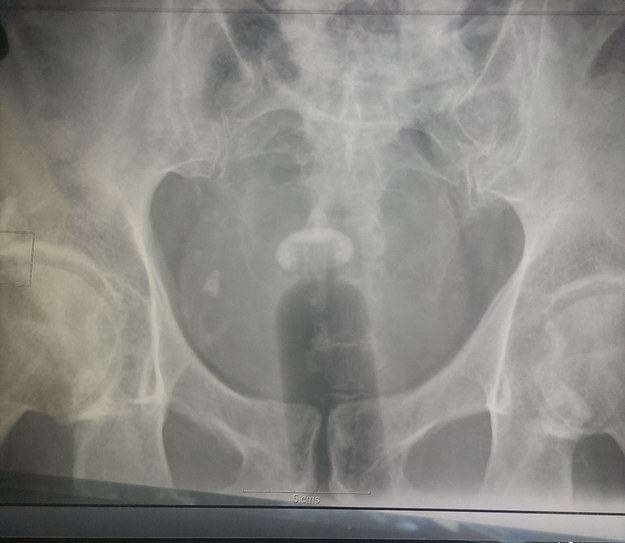

14. Και άλλο μπουκάλι, μαζί με σκοινί για να το τραβήξει μετά έξω… σαν ταμπόν ένα πράμα!